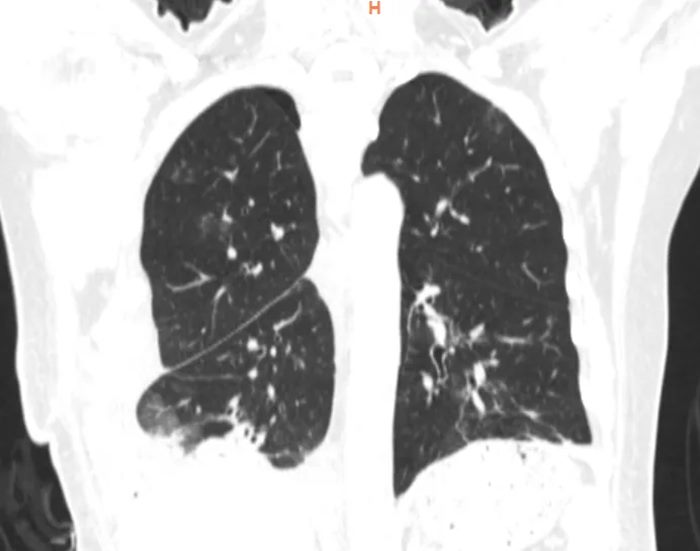

检查发现,马女士右侧胸腔及纵隔内见巨大团片状低密度影,累及左侧胸腔致心脏大血管及气管向左侧胸腔偏移,以脂肪密度为主。肿瘤累及气管、左右主支气管、上腔静脉及主动脉外膜、部分心包、左右下肺静脉,累及并包埋食管及下腔静脉,右肺受压不张。而接下来的手术堪称一场惊心动魄的生命之战。

经过胸外科高兴才主任团队、麻醉科胡强夫主任团队等科室充分准备,输血科魏明主任团队积极备血后,手术按计划如期进行,选择右胸第6肋后外侧切口进胸,因肿瘤体积巨大,占满胸腔,纵隔移位,累及上纵隔、中纵隔、后纵隔,并包绕主动脉及上、下腔静脉、食管。手术空间狭窄,视野受限,术中联合胸腔镜辅助手术,行胸腔及纵隔巨大肿瘤满意切除、心包部分切除。